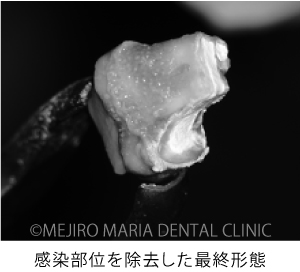

歯牙を抜歯後、メチレンブルーにて染色して破折線を確認しました。破折線に沿って感染部位を除去しましたが、根管内部の構造が非常に複雑なため、最終的な形態は、真ん中の写真のようにしました。

治療のコンセプト通り、根管内部を超音波と歯科用タービンを使用して根尖方向から洗浄しました。その後はMTAにて歯内を封鎖し、抜歯窩へ歯牙を戻して手術は終了しました。